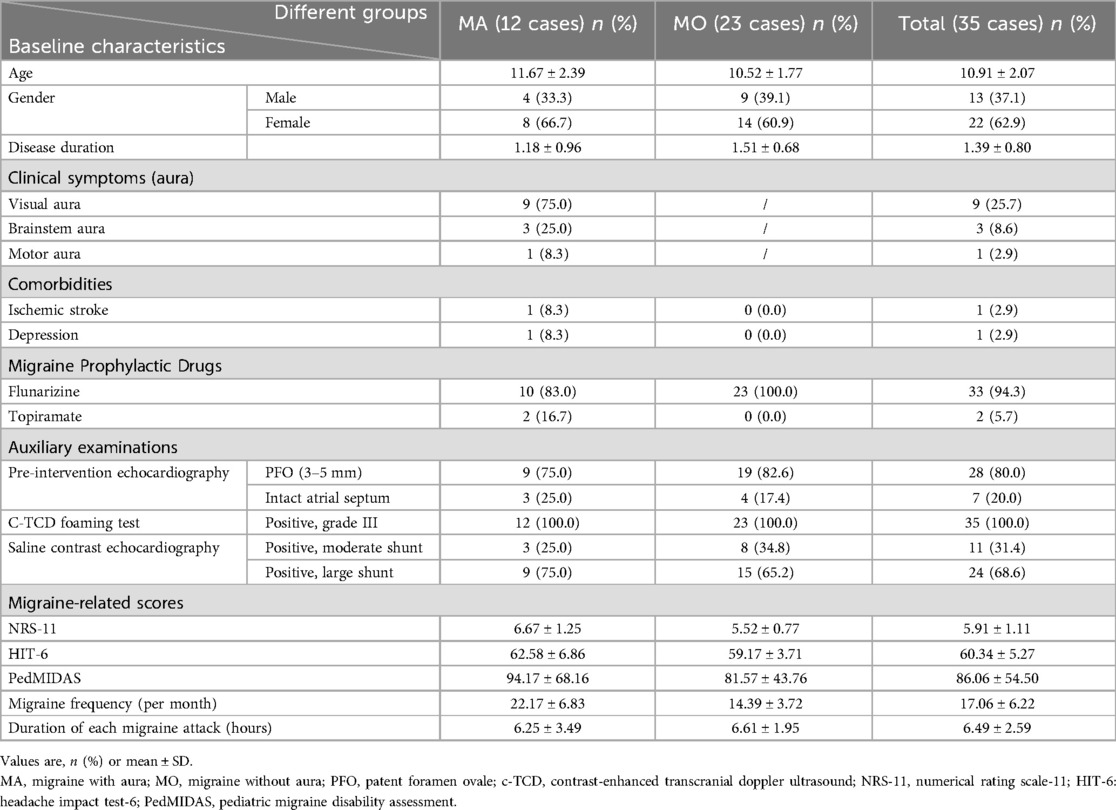

The present study retrospectively analysed data from 35 children including 13 males (37.1%) and 22 females (71%), diagnosed with PFO and migraine who fulfilled the inclusion criteria. The age at onset ranged from 9 to 15 years (10.91 ± 2.07), and the disease duration ranged from 0.5–4 years (mean 1.39 ± 0.80). There were 12 cases of migraine with aura and 23 cases of migraine without aura. The main symptom was headache. The aura in migraine with aura included visual aura (9 cases), brainstem aura (3 cases), and motor aura (1 case, hemiplegic migraine). Primary outcome measures included NRS-11, HIT-6, PedMIDAS, migraine frequency, and duration of each migraine attack, with the following respective mean values: 5.91 ± 1.11, 60.34 ± 5.27, 86.06 ± 54.50, 17.06 ± 6.22 and 6.49 ± 2.59. Baseline characteristics of the children included in this study are summarised in Table 1.

Most patients exhibited varying degrees of improvement in migraine symptoms after PFO closure. At the 1-month follow-up after the intervention, 20 patients (57.1%) achieved complete remission, and 29 (82.9%) experienced a reduction in migraine frequency of >50%. At the 12-month follow-up, 28 patients (80%) achieved complete remission, and 32 (91.4%) experienced a reduction in migraine frequency of >50%. There were no cases of worsening migraine after PFO occlusion. The NRS-11, HIT-6, PedMIDAS, migraine frequency, and migraine duration of all the children three months before the intervention, at 1 month after the intervention, and at 12 months after the intervention are shown in Table 2, which demonstrates a significant decrease in the main clinical outcome indicators of migraines from baseline to 12 months after the intervention. Notably, there were statistically significant differences between pre-intervention and one-month post-intervention data, as well as between pre-intervention and 12-month post-intervention data (p < 0.05). One year after PFO closure, only one patient continued to use the prophylactic migraine medication flunarizine, whereas two patients used analgesics solely during migraine attacks.